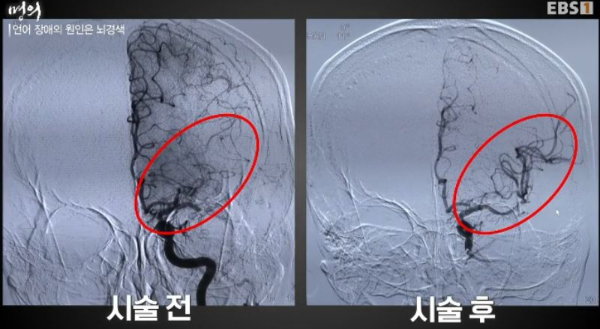

언어 장애의 원인은, 뇌경색

영상진단으로 뇌동맥 중 막힌 부분을 확인하고 시작.

급성 뇌경색 치료를 위한 뇌혈관 중재술

혈전용해제로 막힌 혈관을 개통할 수 없는 경우, 시술을 한다.

사지를 통해 대동맥, 경동맥을 통해 뇌결관으로 카테터를 넣고

혈관을 재개통하고 스텐트 시술까지 필요하면 한 단계씩.